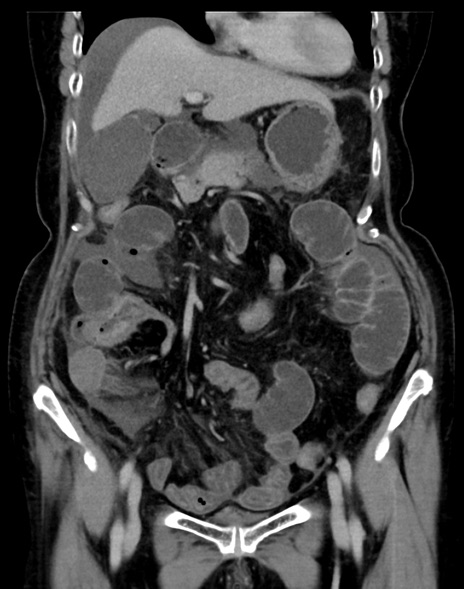

症例13 CT(冠状断像)1日半後